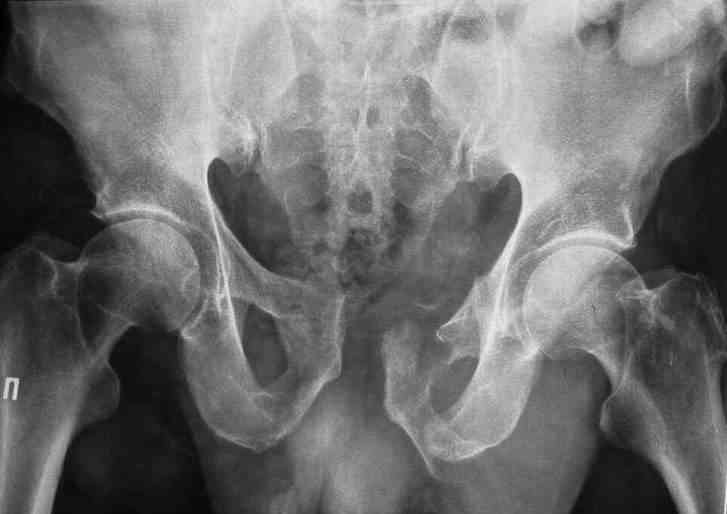

Уважаемые коллеги.У больного оскольчатые переломы левых лонной и седалищной костей со смещением, разрывом симфиза и распространением линии перелома на вертлужную впадину; переломы крыла левой подвздошной кости и правой боковой массы крестца без смещения; разрыв уретры.За последние годы пациент 6 раз оперирован на передней брюшной стенке (гнойный аппендицит срединным доступом, вентральная послеоперационная грыжа и паховые грыжи с обеих сторон, оперированные по 2 раза каждая). Остались 3 грубых втянутых рубца после этих операций. В настоящее время имеются 2-сторонние паховомошоночные грыжи (на одной из КТ-грамм указаны стрелками), из которых левая - значительных размеров. Мошонка огромная, однако, не напряженная. Состояние больного на сегодняшний день относительно удовлетворительное, кровопотеря компенсирована, мочевой пузырь катетеризирован.Прошу мнения сообщества по следующим вопросам: выполнять ли в таких условиях остеосинтез? Если да, то в какой последовательности (отдельно или одним этапом с герниотомией)? Объем остеосинтеза? Доступ?

Доброго времени суток, Сергей. В данном случае фиксация переднего полукольца желательна, так как имеется разрыв уретры (вероятнее всего его мембранозного отдела). Иными словами, нужно восстановить тазовую диафрагму. Доступ - надлобковый в сочетании с неполным подвздошно-паховым доступом по Letournel слева. Нет необходимости в полной визуализации внутренней подвздошной ямки, а, следовательно, и в отсечении мышц от гребня подвздошной кости. Напротив, тщательное выделение элементов в передних отделах создаст благоприятные условия, как для синтеза, так и для герниопластики. После выделения и остеосинтеза (реконструктивная пластина 3-4 отверстия справа и до внутренней подвздошной ямки - слева) выполнить герниотомию. Грыжи рецидивирующие и скорее всего без пластики (к примеру по Lichtenstein) не обойтись. Да, если выполнены уретрограммы и имеется полный отрыв уретры или повреждена ее значительная часть, то нужно определиться с цистостомией. Перкутанная эпицистостомия в послеоперационном периоде будет более предпочтительна. В задних отделах вертикальной нестабильности нет.